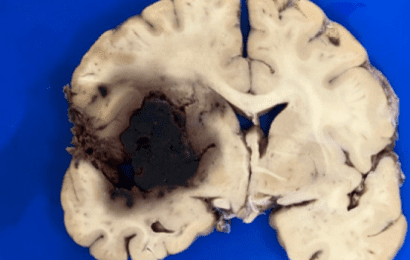

Preprint: Autopsies reveal Covid-19 brain damage

SARS-CoV-2 related coagulation disorders are the main cause of the brain tissue damage. Most of the brain damage was related to thrombosis. We investigated the neuroinvasive potential of SARS-CoV-2, searching … Continue reading Preprint: Autopsies reveal Covid-19 brain damage